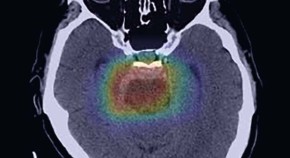

• Previous open-label trials testing glial cell line-derived neurotrophic factor (GDNF) family ligands in Parkinson disease have shown promising clinical effects. However, in placebo-controlled trials, the treatments have failed. A new randomized placebo-controlled trial of intraputamenal delivery of GDNF designed to resolve this conundrum has again failed to do just that.

• Agnete Kirkeby

• Roger A. Barker

News & Views